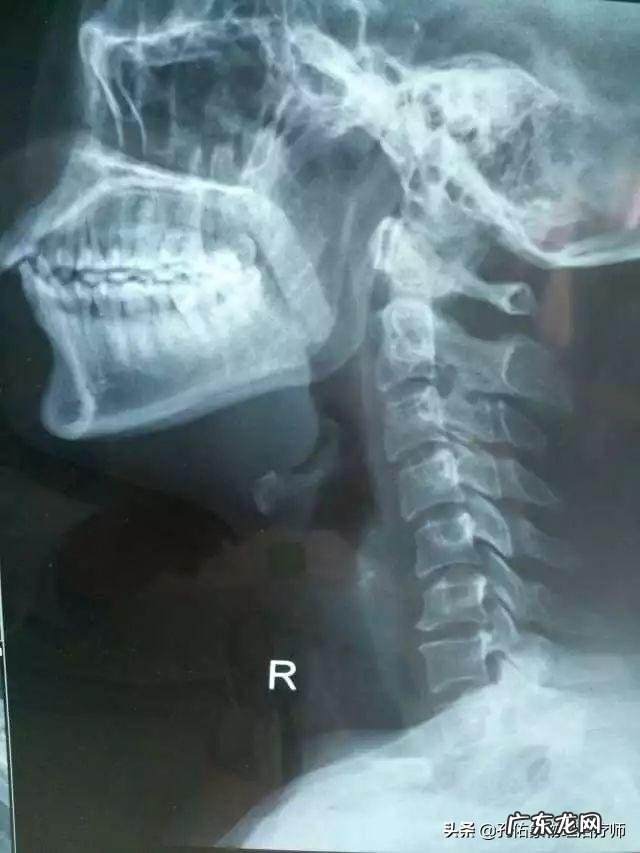

去医院拍片 , 都是颈椎生理曲度变直

当颈曲变直发生后 , 一系列的情况也同时发生了改变 , 比如我们的关节、肌肉、韧带、筋膜、血液等 , 这些的改变会让我们颈椎终于不堪重负 , 出现更多新的问题 。

所以在这种情况下 , 颈曲变直会成为各种颈椎病如韧带增生、钙化、颈椎间盘突出、椎动脉狭窄等的结构和病理基础 。